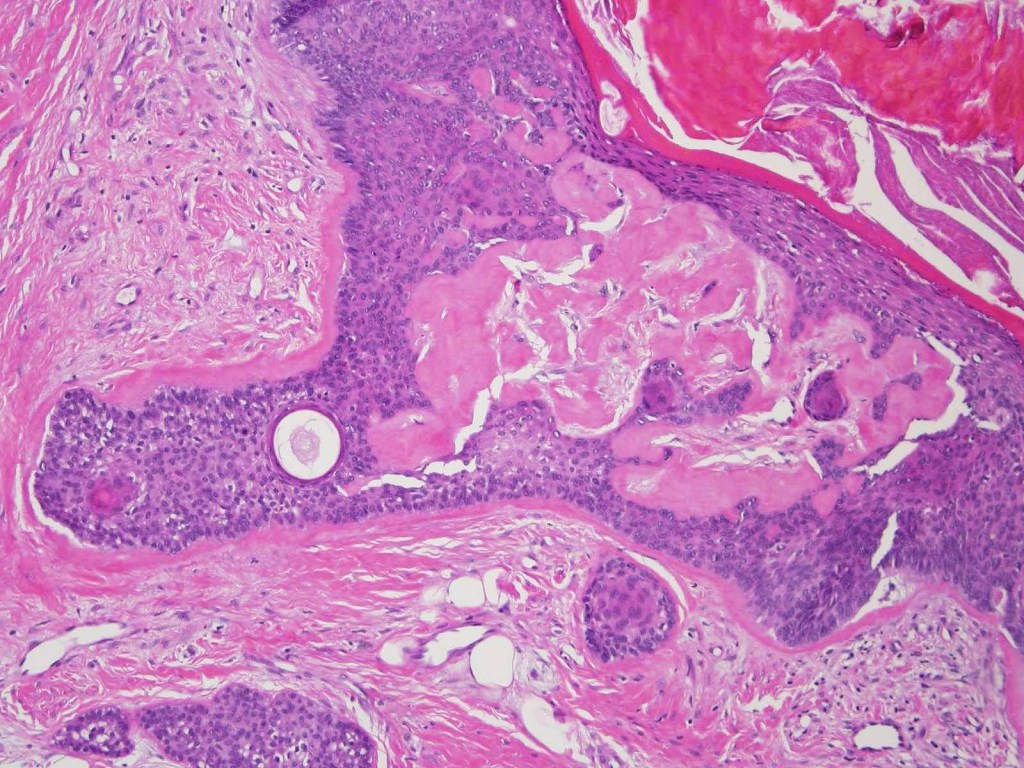

•Well circumscribed unencapsulated, nodular/multinodular silhouette composed of an admixture of epithelial & mesenchymal elements

•Mixed epithelial component including nests & cords of epithelium with abundant, eosinophilic cytoplasm & small vesicular nuclei

•Glandular differentiation sometimes showing apocrine differentiation

•Ductal differentiation

•Cribriform/retiform appearance occasionally evident

•Follicular & sebaceous differentiation

•Keratocysts & squamous foci

•Stromal sclerosis & hyalinization

•Myxoid change

•Chondroid foci